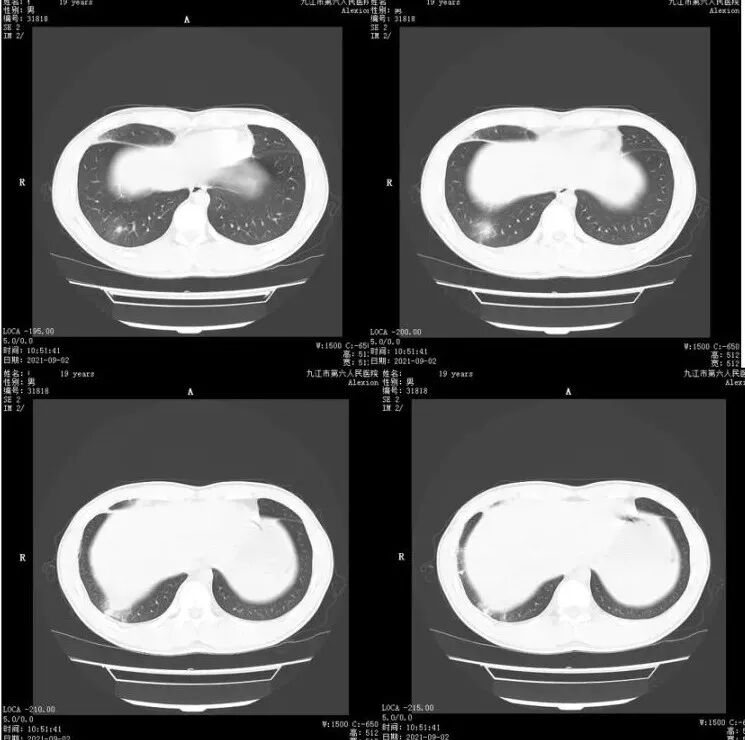

青年男性,右肺多发结节斑片状高密度影,周围较多晕,右上肺结节内见空洞形成。实验室检查嗜酸性粒细胞增高,考虑寄生虫感染,鉴别嗜酸性粒细胞肺炎

男,青少年,右肺中下叶斑片状高密度,密度不均,其内实性成分边缘平直,周围磨玻璃灶,边界模糊,化验嗜酸性粒细胞增高,炎症,考虑嗜酸性细胞性肺炎,

年轻男性,嗜酸性细胞明显升高,多发类结界病变,边界模糊,部分空洞,空洞内无气液平,似隧道,考虑肺寄生虫病,吸虫?

年轻男性,右肺多发斑片影边缘模糊,有空腔改变,北京友谊医院就诊记录,化验嗜酸高,考虑寄生虫

右肺多发实变影伴磨玻璃影,局部空洞改变,可疑轨道征

血EOS明显升高

年轻男性,右肺中叶及下叶胸膜下多发结节,周围磨玻璃晕,部分似隧道,实验室嗜酸性粒细胞增高,考虑肺寄生虫,鉴别隐球菌

男,19岁,既往肺炎病史,CT示右肺多发实变影伴周围磨玻璃影,边界不清,中叶病变伴空洞,嗜酸性粒细胞增高,考虑寄生虫或嗜酸性细胞性肺炎可能

年轻男性,嗜酸性细胞明显升高,右肺多发斑片影,边界模糊,局部空洞,似隧道,考虑肺寄生虫病可能性大,真菌待排。

青少年,右肺中、下叶斑片状,结节状高密度,密度不均,内见扩张的支气管,周围磨玻璃影,嗜酸性粒细胞增高,考虑感染性病变,嗜酸性细胞性肺炎,寄生虫感染。

19岁,右肺多发片状及结节状高密度影,边缘模糊,见磨玻璃密度影,部分有空洞,呈薄壁,内壁规整,临近叶间胸膜增厚,考虑炎性肉芽肿性病变,化验嗜酸高,嗜酸性细胞性肺炎

胸部CT:右肺中下叶多发结节影、斑片影,周围模糊GGO,右中叶空洞结节,内壁光滑无气液平。右侧叶裂增厚。考虑:PC?寄生虫?鉴别药物、支气管中心肉芽肿病等。